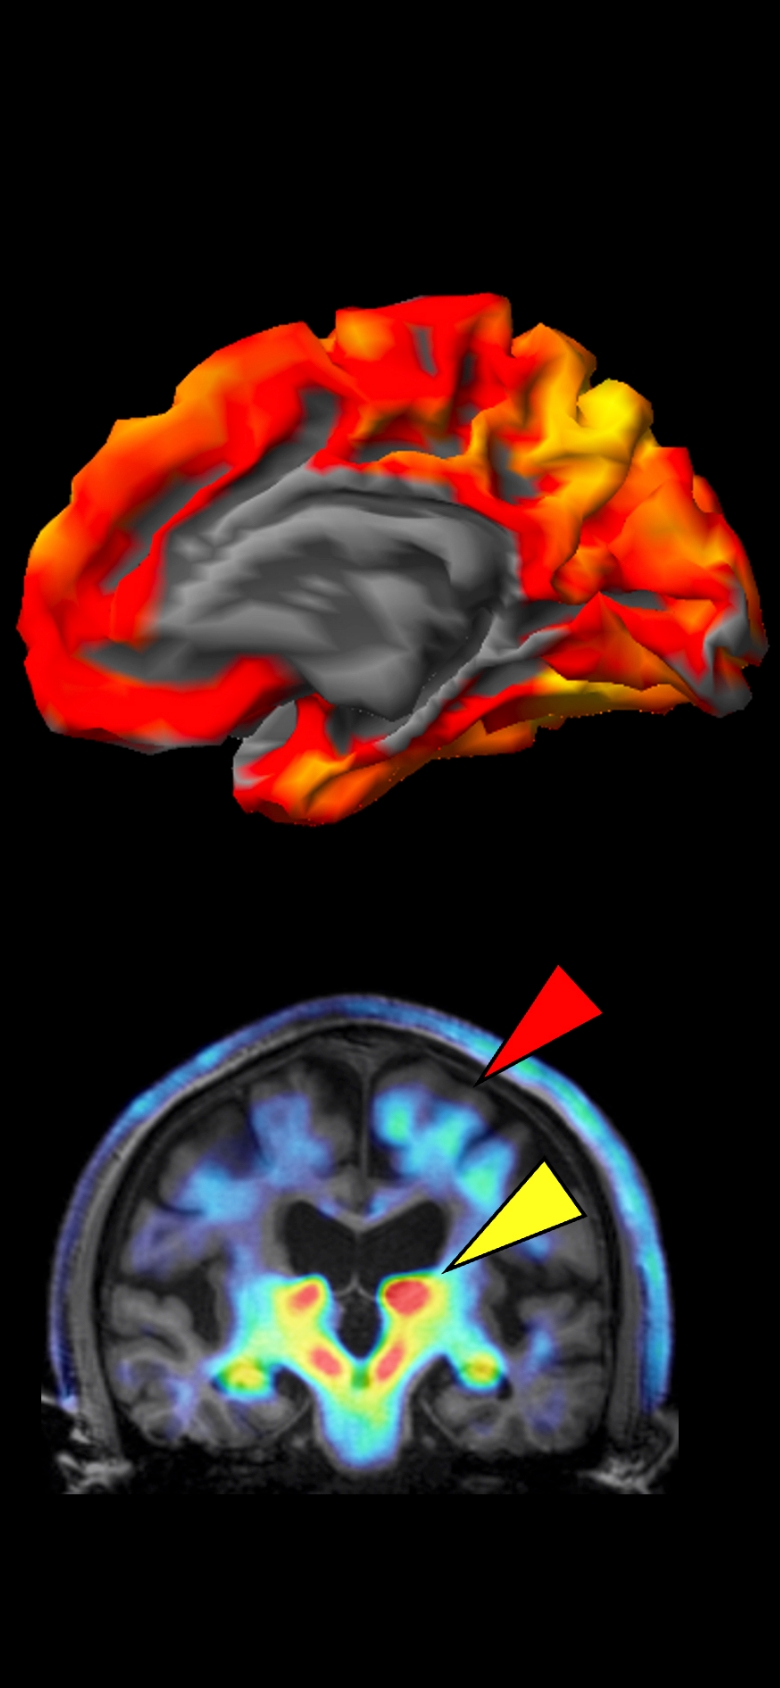

Early detection and modulation of the dementia pathogenesis based on the concept evolving from glial pathology to senoinflammation

さらに、2023年8月に政府が提唱した「認知症・脳神経疾患研究開発イニシアティブ」を受け、ムーンショット目標7の枠組みのもと、認知症克服を目的とした新たな研究が加速しています。2024年11月からは、「脳内セノインフラメーション」を含む3件の新規プロジェクトが本格的に始動しました。